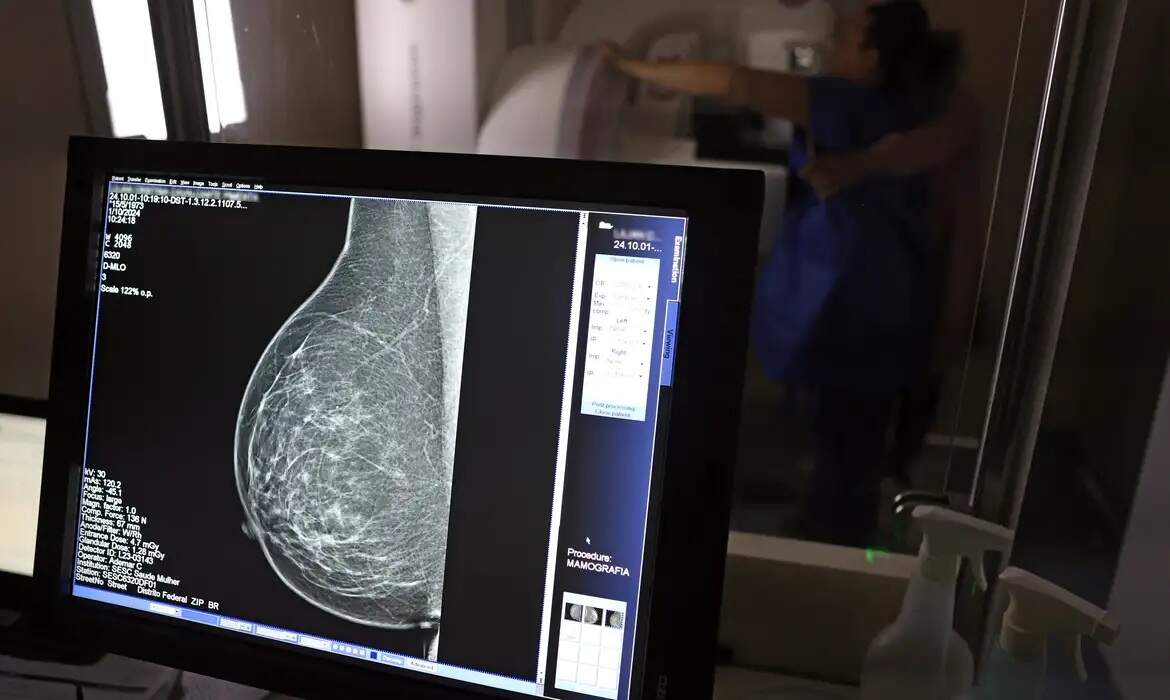

Pela primeira vez, Porto Alegre zerou a fila por radioterapia e tratamentos oncológicos de mama na rede do Sistema Único de Saúde (SUS). A marca foi alcançada na última sexta-feira (11), com o encaminhamento de todos os pacientes que ainda aguardavam por tratamento.

Conforme a prefeitura, a secretaria de Saúde tem conseguido reduzir, em média, mil pessoas por semana das filas desde abril. Além de eliminar a fila, na oncologia de mama, o tempo médio para agendamento, que era de 11 dias em dezembro, caiu para dois dias em junho, enquanto na radioterapia oncológica, a espera caiu de 26 dias para dois dias.

No caso da oncologia de mama, um dos reforços foi o início do centro de oncologia do Hospital Vila Nova e a operação de um novo mamógrafo, que vem contribuindo para acelerar os diagnósticos e garantir encaminhamento ágil a biópsias e tratamentos. A oferta ampliada de exames nas Ofertas de Cuidados Integrados (OCIs) também foi decisiva nesse processo.